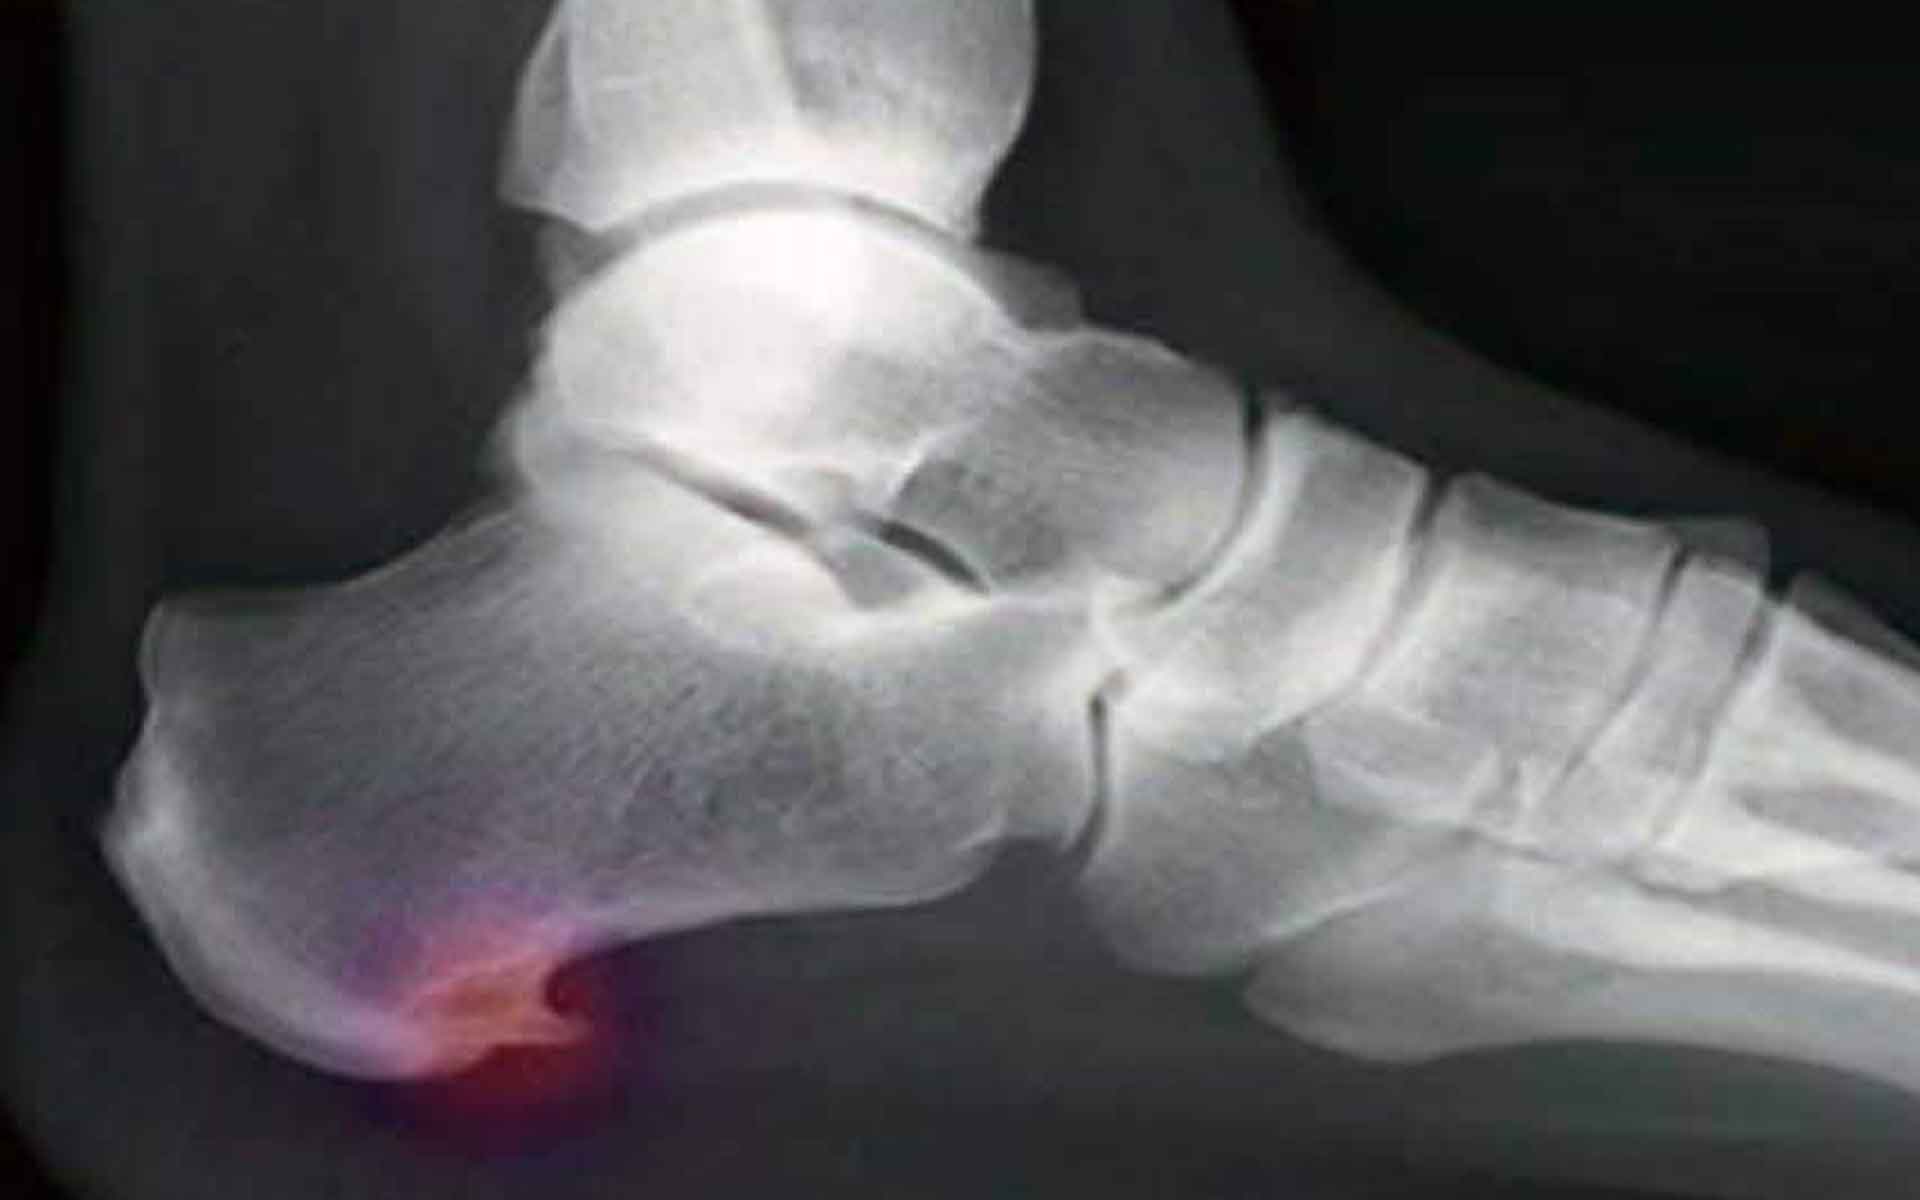

10 datos poco conocidos sobre el espolón calcáneo

¿Qué sabemos realmente de esta condición tan dolorosa que puede acechar debajo de la superficie de tus pies? Hemos compilado algunos de los datos más interesantes y estadísticas sobre los espolones calcáneos, para ayudarte a entender que son realmente y cómo manejar esta condición.

Si tienes Fascitis plantar, ya estás familiarizado con el dolor matutino, esos primeros pasos insoportables al levantarte de la cama. Pero ¿por qué sucede esto? Los espolones calcáneos son frecuentemente el culpable número uno de este tipo de dolor, ya que las calcificaciones generadas se incrustan en los tejidos blandos después de un periodo de inactividad.

Aproximadamente el 38 porciento de la población tiene un espolón calcáneo, pero muchos no lo saben todavía. Un estudio que se ha llevado a cabo durante un periodo de 45 años encontró que mucha gente que había desarrollado un espolón calcáneo no se veía reflejado en dolor en el talón.

Aunque los espolones calcáneos y la Fascitis plantar no siempre van de la mano, alrededor del 70 porciento de las personas con Fascitis plantar tienen espolones calcáneos dolorosos. Se cree que el cuerpo crea los espolones calcáneos como medida de protección en respuesta al daño provocado en la fascia plantar.

Los investigadores creen que los espolones calcáneos son un intento del cuerpo para proteger la fascia plantar y otros tejidos del daño y el esfuerzo. Cuando este daño ocurre, las células son destinadas a esa área y empiezan a depositar calcio. Con el tiempo, esos depósitos, pueden acabar construyendo protrusiones puntiagudas que causan dolor, ciertamente es una ayuda equivocada.

Los espolones calcáneos se forman en la base del talón, mientras que los causados por tendinitis aquílea se forman en la parte trasera del talón. Aunque estas condiciones son diferentes, hay estudios que han encontrado la correlación entre ellos.